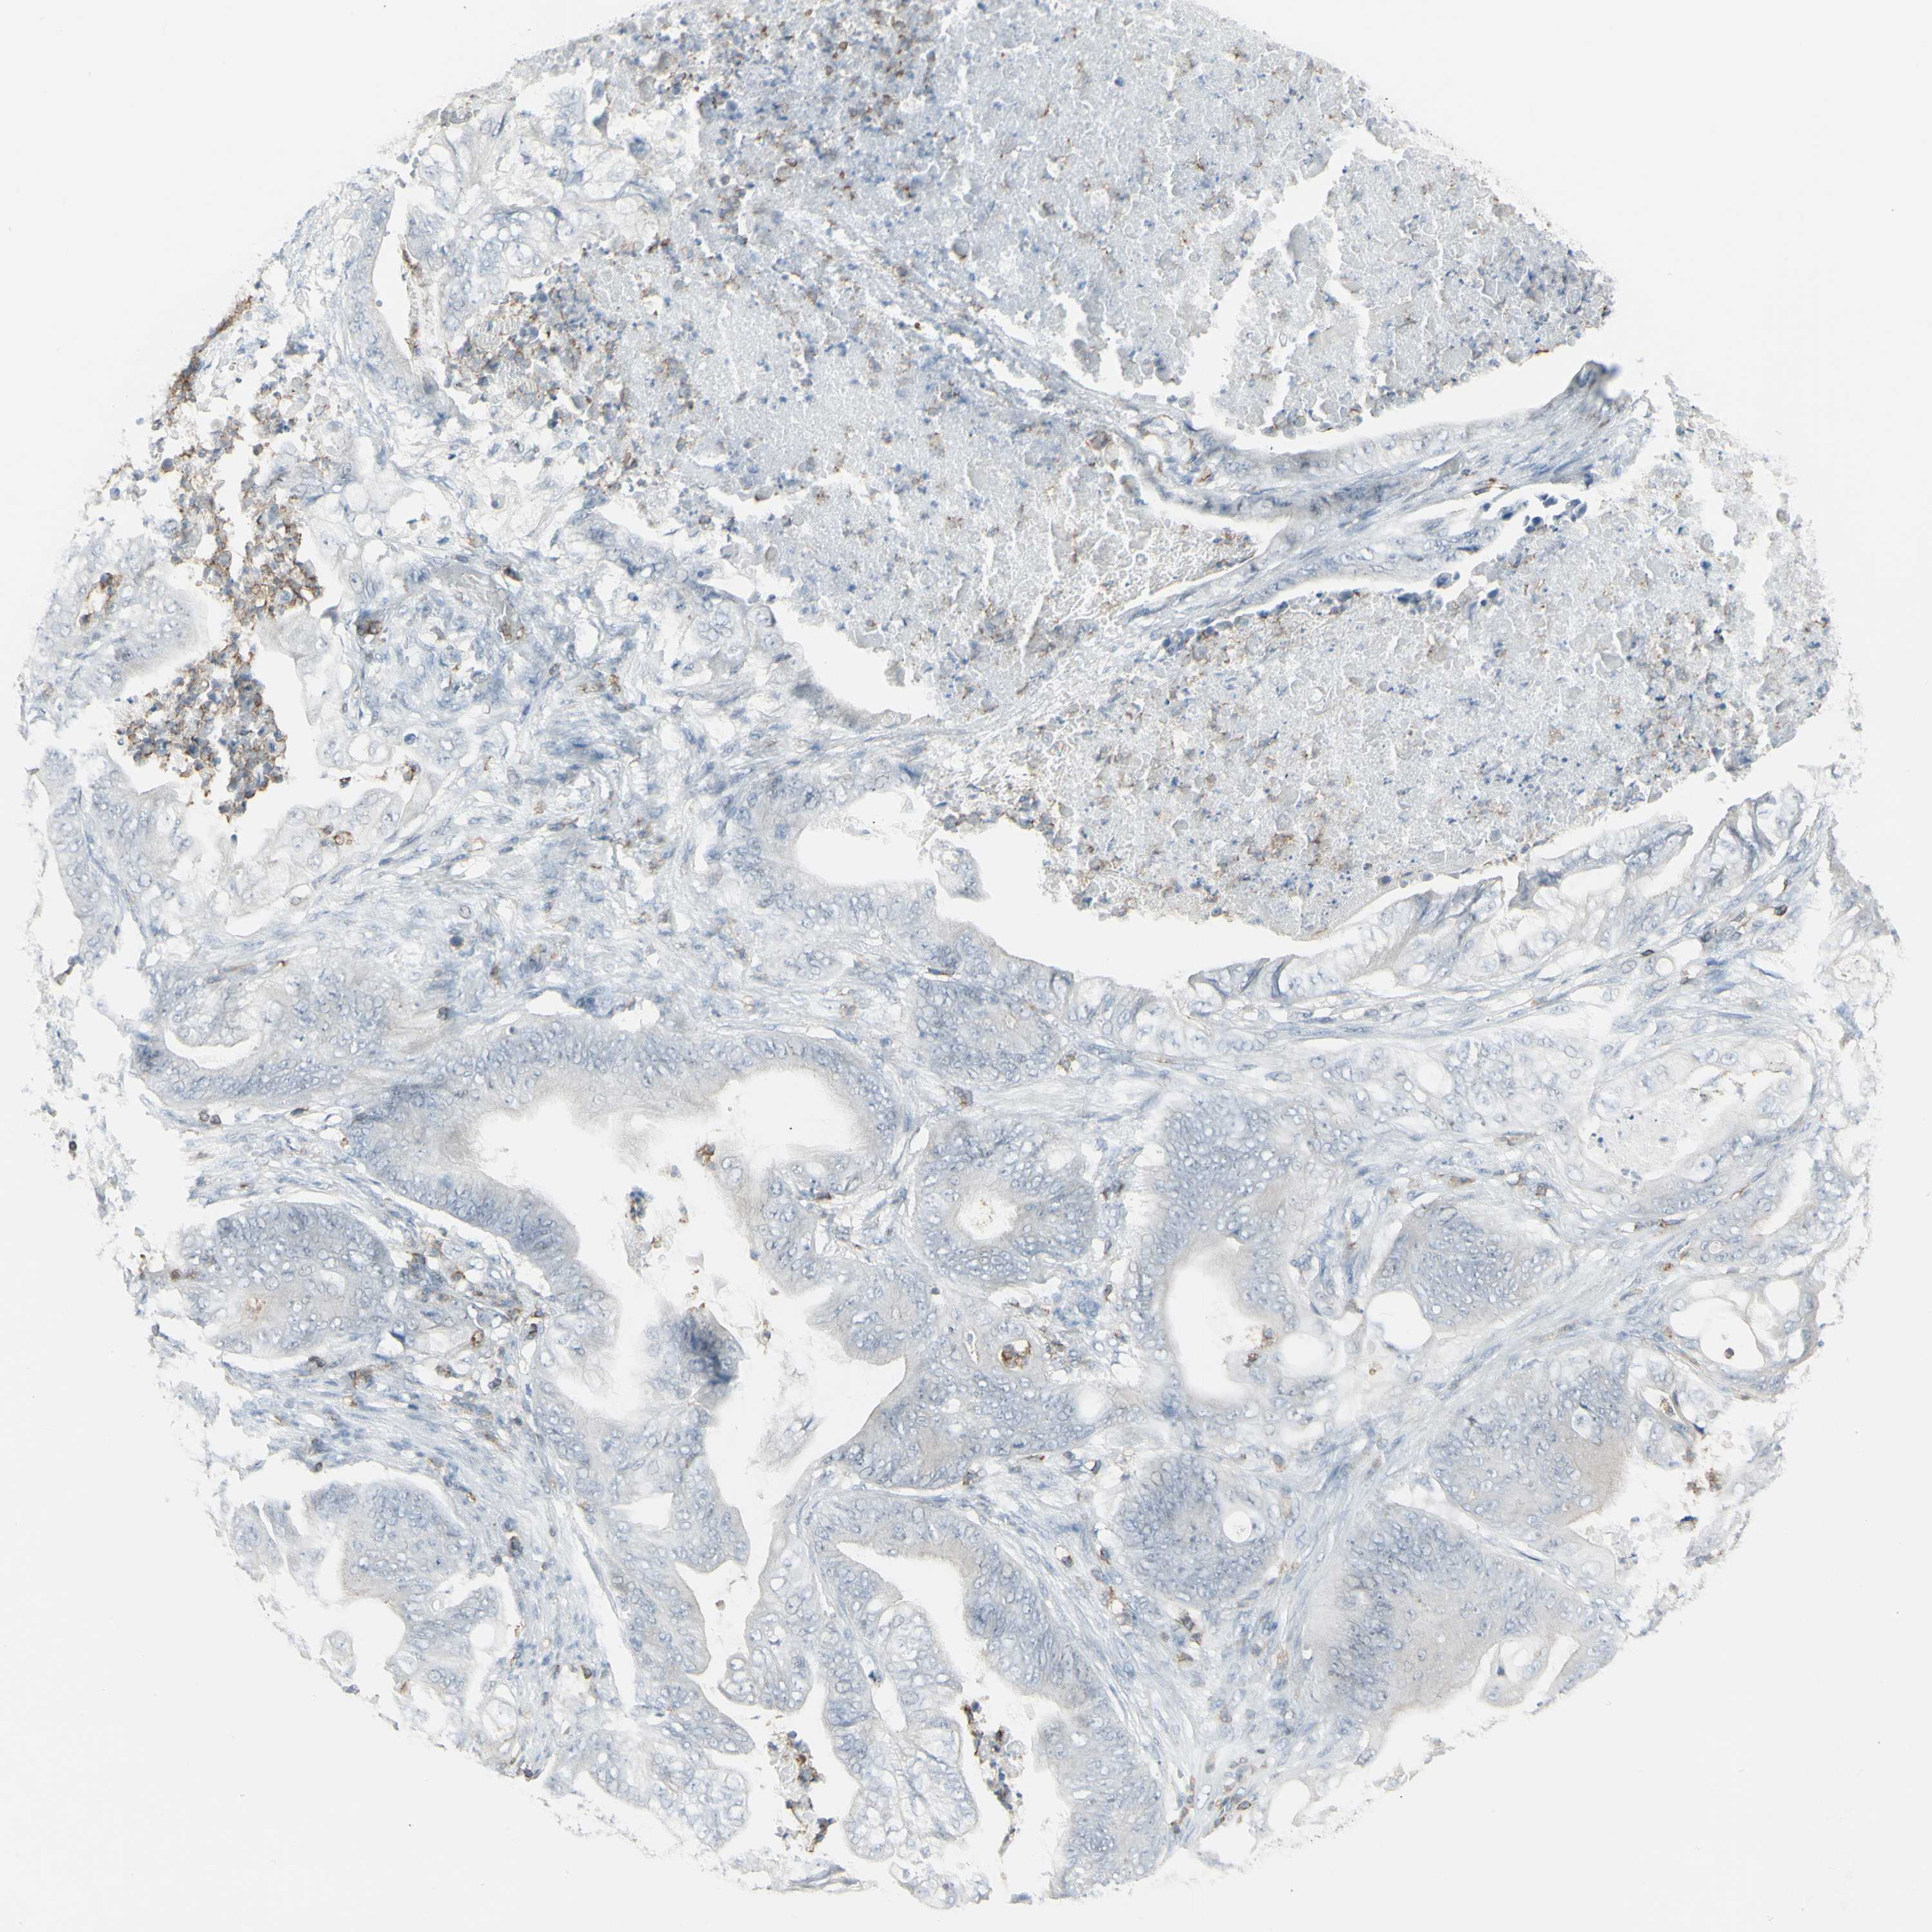

STOMACH CANCER - Protein expressioni

A mouse-over function shows sample information and annotation data. Click on an image to view it in a full screen mode. Samples can be filtered based on level of antibody staining by selecting one or several of the following categories: high, medium, low and not detected. The assay and annotation is described here.

Note that samples used for immunohistochemistry by the Human Protein Atlas do not correspond to samples in the TCGA dataset.

Antibody stainingi

Antibody staining in the annotated cell types in the current human tissue is reported as not detected, low, medium, or high, based on conventional immunohistochemistry profiling in selected tissues. This score is based on the combination of the staining intensity and fraction of stained cells.

Each image is clickable and will lead to virtual microscopy that enables deeper exploration of all samples and also displays staining intensity scores, fraction scores and subcellular localization as well as patient and tissue information for each sample.

Antibody HPA010964

Staining

High

Medium

Low

Not detected

Intensity

Strong

Moderate

Weak

Negative

Quantity

>75%

75%-25%

<25%

None

Location

Nuclear

Cytoplasmic/membranous

Cytoplasmic/membranous,nuclear

Adenocarcinoma, NOS